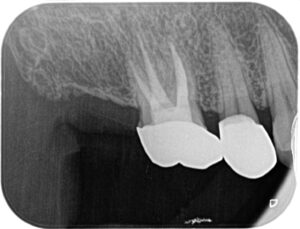

術後1年:根尖病変は治癒し、再発は認められません。